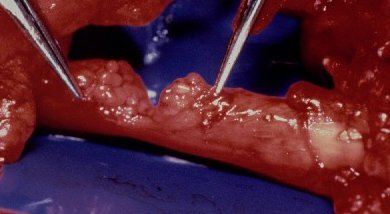

Partial nerve lacerations have a particular priority, as even a delay of a few weeks in repair increases the risk of producing additional damage from dissection and attempts at repair. (case of Dr. Graham Lister)